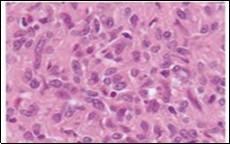

Ultrastructural evaluation is devoid of pertinent cellular features. However, modified endothelial cells, smooth muscle cells, striated muscle cells, histiocyte- like cells, fibroblast- like cells and miniature, interdigitating cellular processes conjoined by desmosome- like junctions are discerned5, 6. Figure 1, Figure 2, Figure 3, Figure 4, Figure 5, Figure 6, Figure 7, Figure 8.

Figure 3.Angiomatoid fibrous histiocytoma enunciating elliptical and spindle-shaped cells with moderate eosinophilic cytoplasm and intermixed lymphocytes and plasma cells 10.